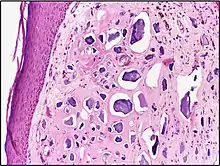

![]() | Foam cells | Histopathology of cholesterolosis of the gallbladder, with annotated foam cell | Category: Foam cell | Foam cell |